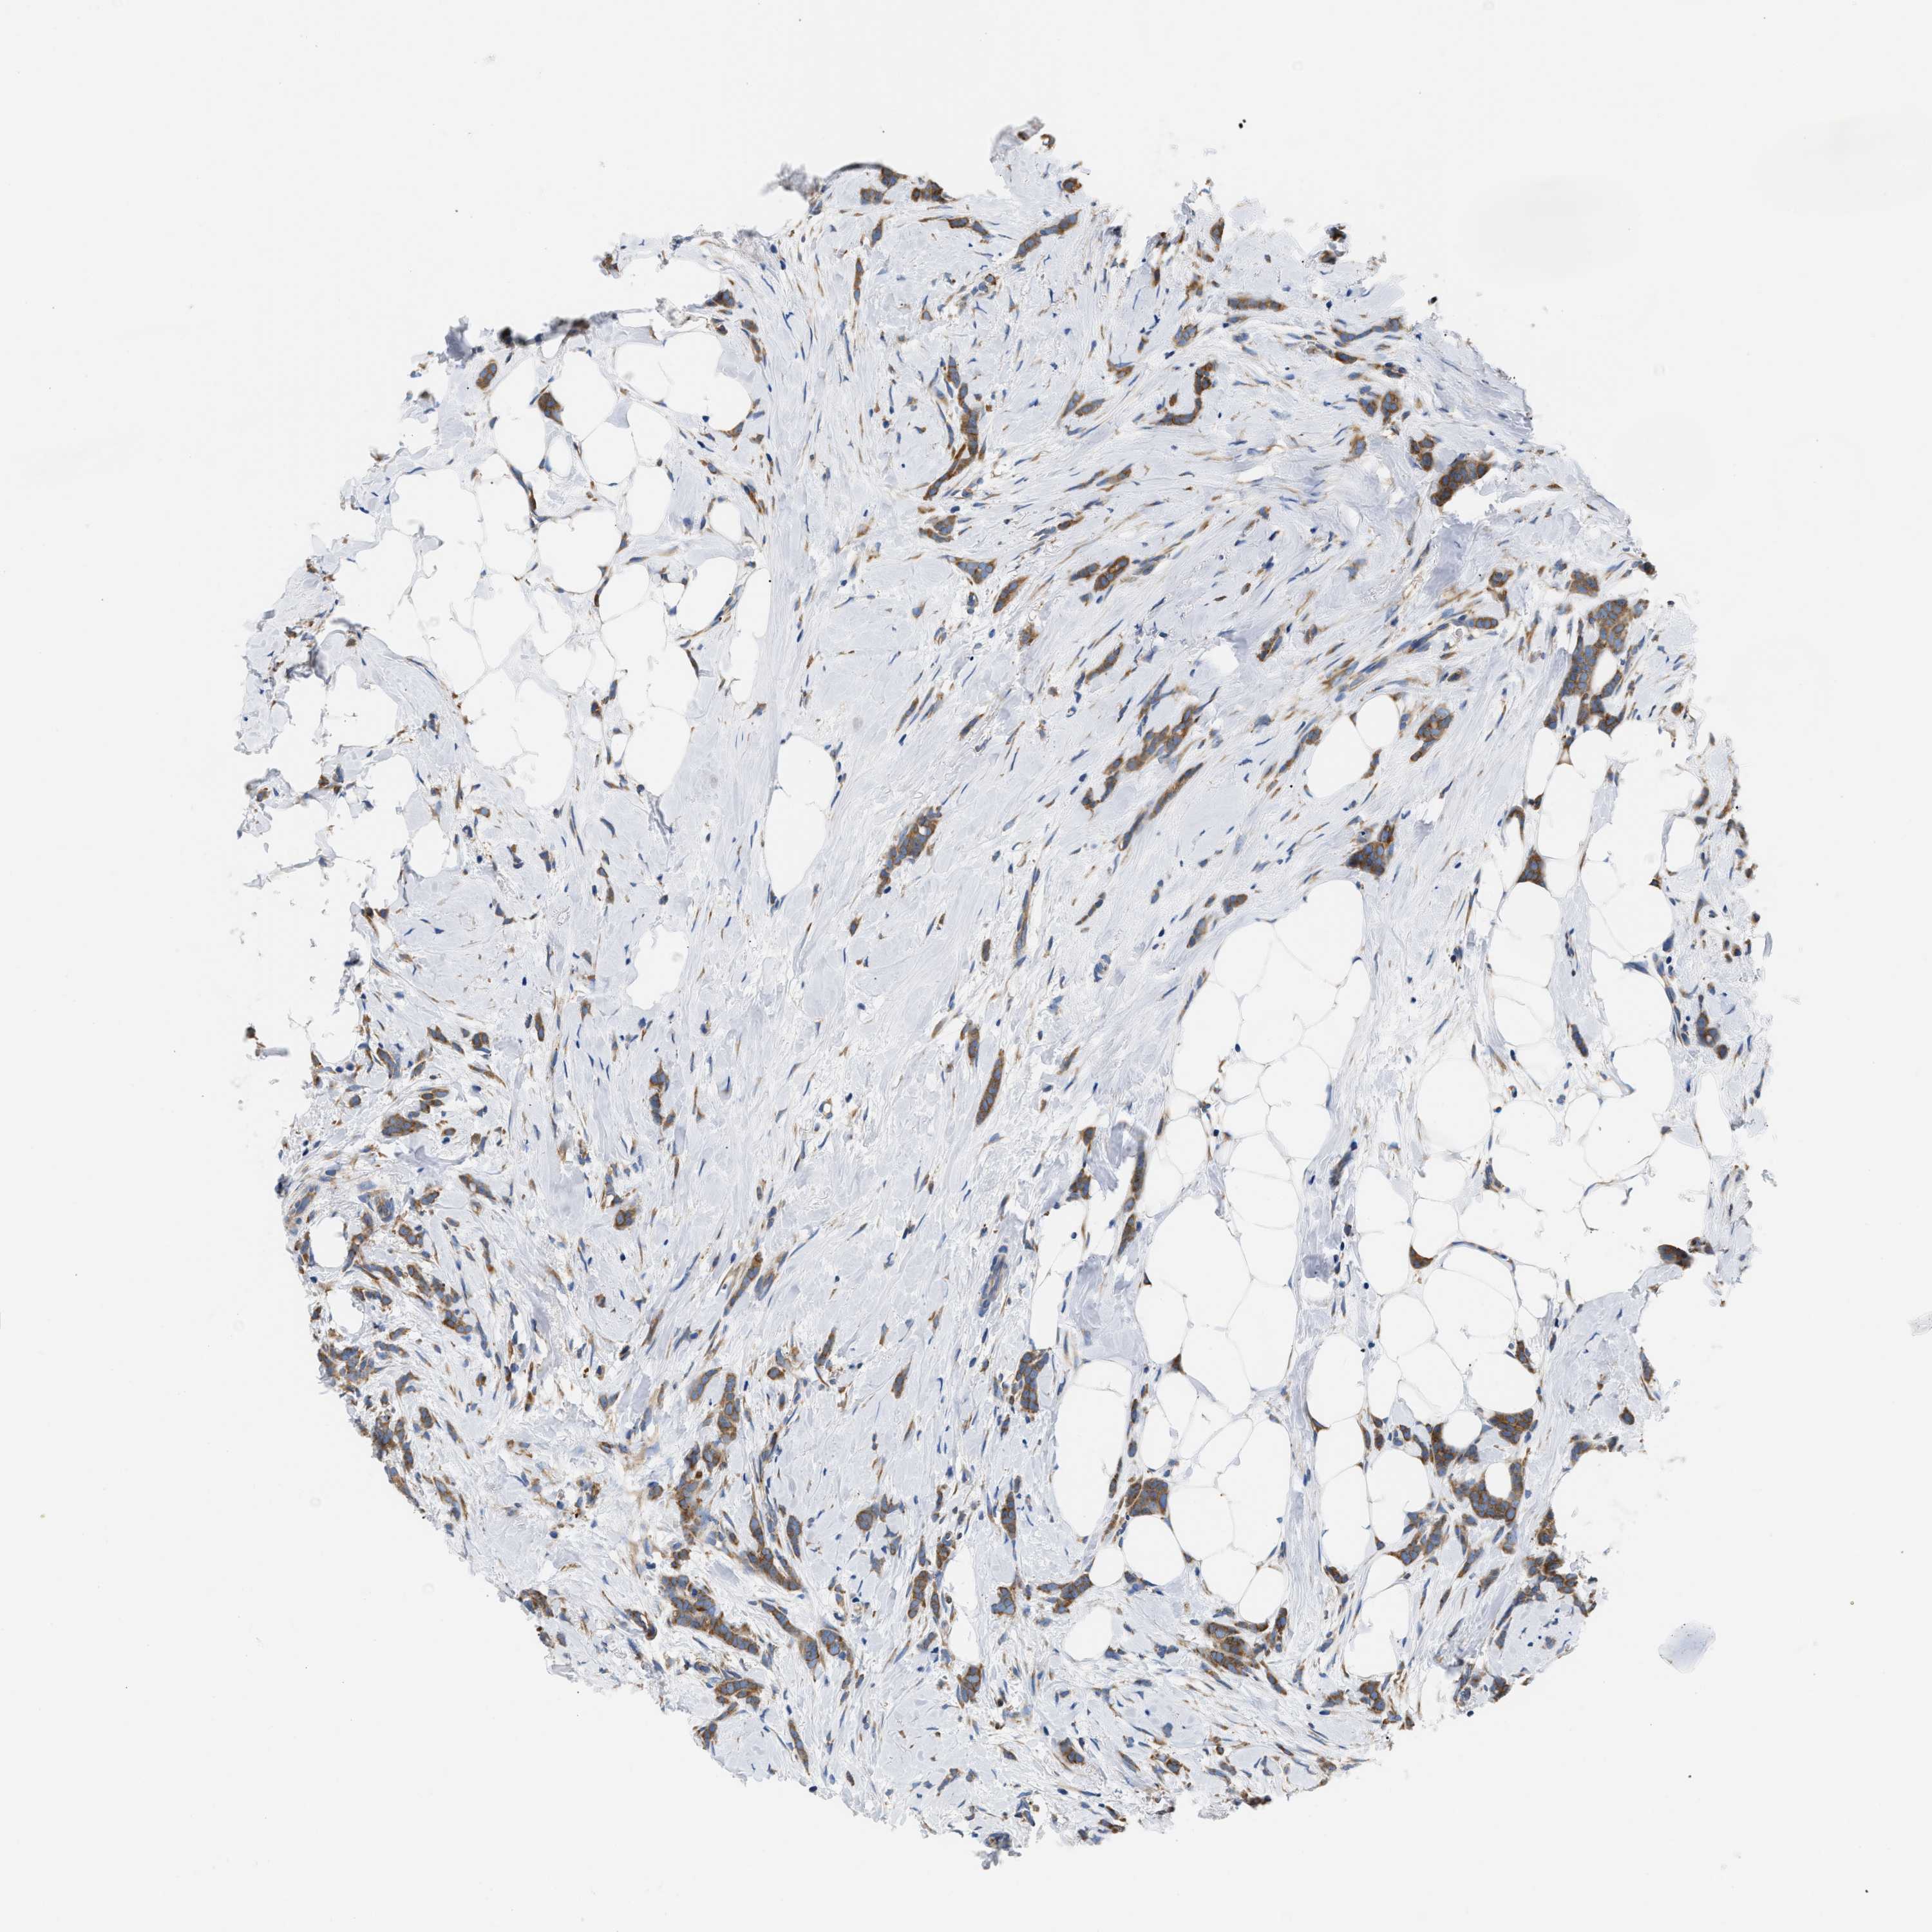

CANCER BREAST CANCER Show tissue menu

BRCA TCGA BRCA VALIDATION PROTEIN EXPRESSION